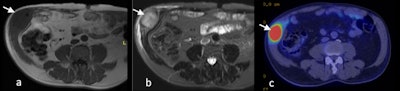

Axial contrast-enhanced CT images of (A) perinephric hematoma (white arrow), and (B) subcapsular hematoma (white arrow) postextracorporeal shock wave lithotripsy in two patients.

Axial contrast-enhanced CT images of (A) perinephric hematoma (white arrow), and (B) subcapsular hematoma (white arrow) postextracorporeal shock wave lithotripsy in two patients.One of the most common complications of ESWL is the formation of a perinephric or subcapsular hematoma, with an incidence of approximately 4%. The risk of a renal hematoma post-ESWL is significantly increased with increasing patient age, use of a therapeutic dose of low molecular weight heparin and the presence of an untreated urinary tract infection. The resultant compression of the kidney from the perinephric or subcapsular hematoma has been reported to cause systemic hypertension, also known as Page kidney.